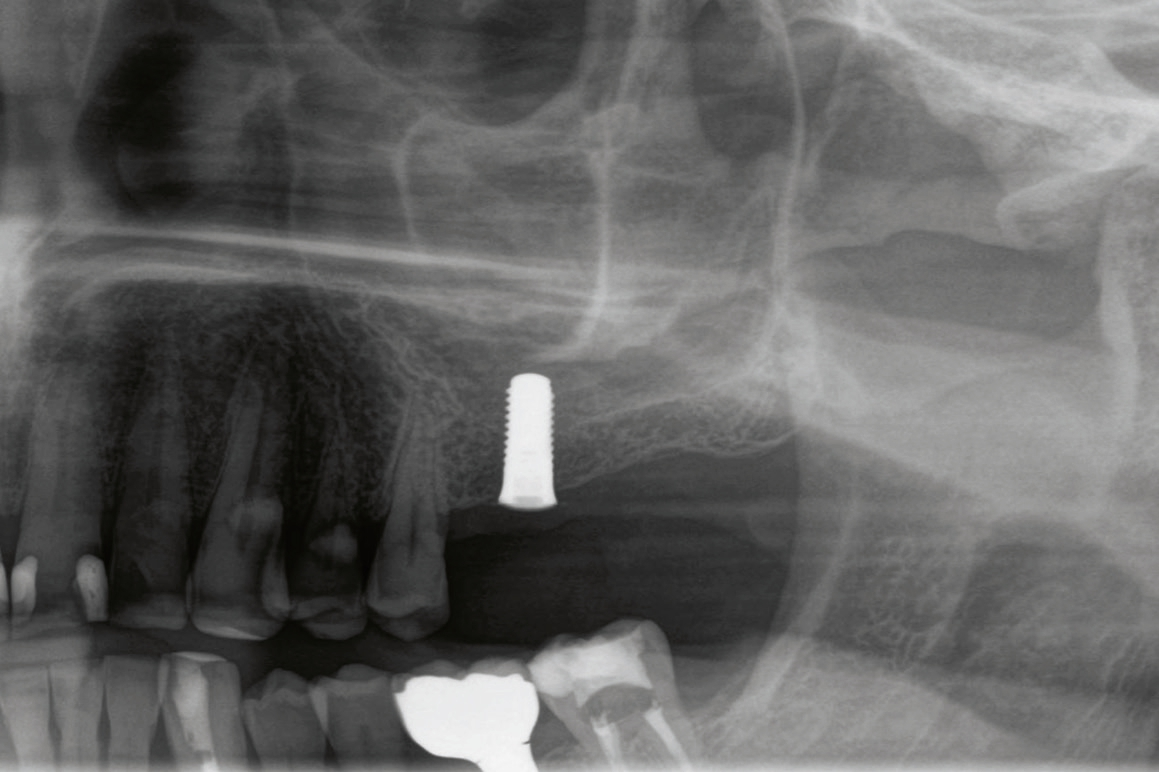

60-jähriger, männlicher Patient mit seit etwa acht Jahren bestehender Freiendsituation in regio 26/27. Drei Jahre zuvor wurde auf Position 36 ein PURE Monotype erfolgreich eingesetzt und prothetisch versorgt. Insgesamt ausgezeichnete Mundhygiene und absolut reizfreie Situation an 36. Der Wunsch des Patienten war nun die Versorgung der Position 26 mittels eines Keramikimplantates ohne größere chirurgische Intervention. Nach Anfertigung der dreidimensionalen Aufnahme (DVT) stellten sich ein ausreichendes transversales Knochenangebot und eine vertikale Höhe von ca. 5 – 6 mm zur Kieferhöhle dar, so dass ein interner Sinuslift und die Verwendung eines zweiteiligen Implantates geplant wurden. Das geringe vertikale Knochenangebot und die reduzierte Qualität verglichen mit dem Unterkiefer hätten bei Verwendung eines einteiligen Implantates mit transgingivaler Heilung ein Risiko für die erfolgreiche Osseointegration dargestellt. Zur Vorbereitung wurde die leichte basale Schleimhautschwellung beim Hals-Nasen-Ohren Arzt abgeklärt und der Patient führte täglich Nasenspülungen durch.

Nach lokaler Anästhesie wurden ein Kieferkammschnitt und eine nur minimale Mobilisation des Mucoperiostlappens durchgeführt. Beim internen Sinuslift nach Summers wird die Pilotbohrung bis ca. 1 mm vor die Begrenzung der Kieferhöhle vorgenommen und je nach Knochenangebot und Qualität mittels verschiedener Osteotome (Institut Straumann) weiter aufbereitet. Unabdingbar ist dabei die regelmäßige Kontrolle der Unversehrtheit der Schneider‘schen Membran durch einen „Nasenblasversuch“. Nach erfolgreicher Aufbereitung des Lagers konnte ein Implantat Größe 4,1/10 mm sehr gut primärstabil inseriert werden, anschließend primärer Wundverschluss mittels 5/0 monophiler Naht. Nach vier Monaten erfolgte die minimalinvasive Freilegung und Applikation des Gingivaformers.